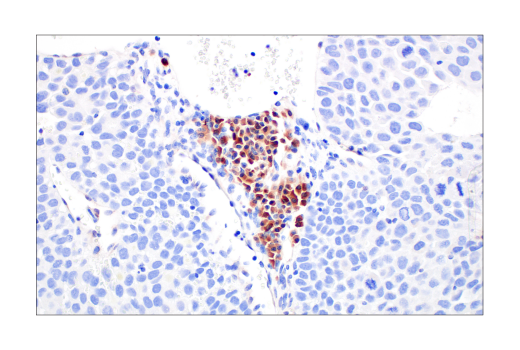

W, IHC-Bond, IHC-P, FC-FP

W: Western Blotting IHC-Bond: IHC Leica Bond IHC-P: Immunohistochemistry (Paraffin) FC-FP: Flow Cytometry (Fixed/Permeabilized)